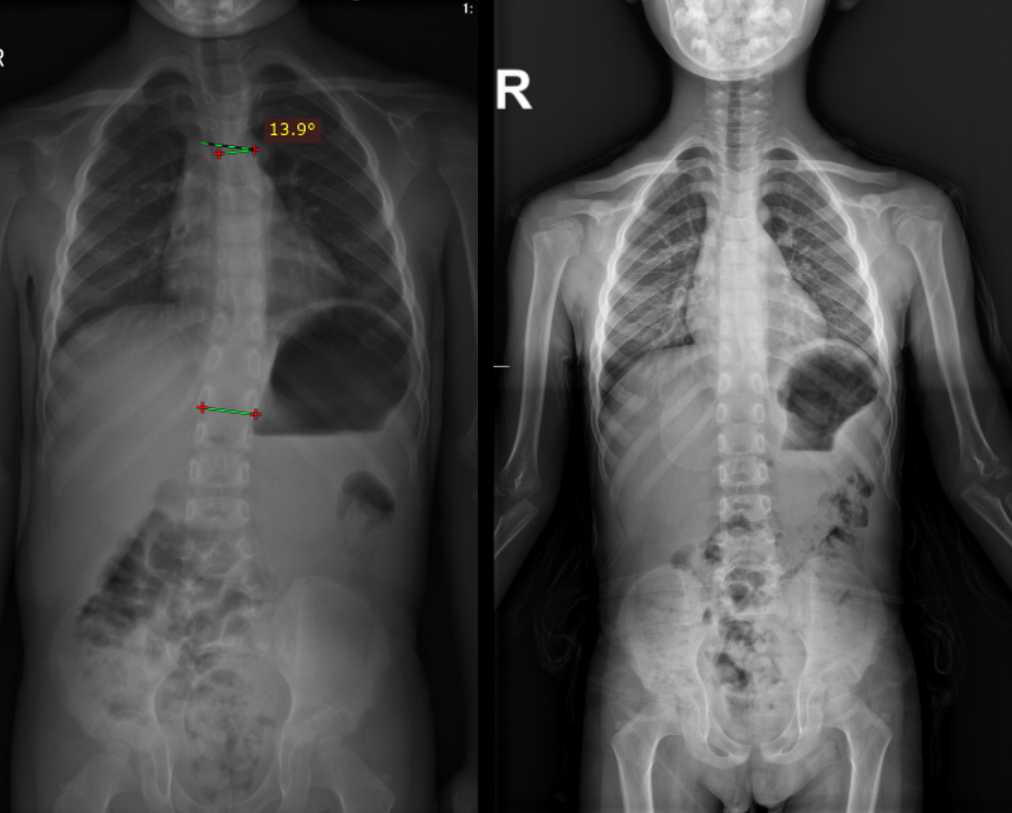

患者男,7岁,家族遗传性骨骼发育不良,体态姿势不正遂至本院就诊。2020年8月拍摄脊柱全长X线片,显示双下肢不等长、双髋关节、脊柱畸形,骨盆倾斜并引起脊柱侧弯,影像检查显示Cobb角胸弯13.9°。

复查

2021年2月,矫形鞋垫佩戴6个月后至医院复查,再次拍摄脊柱全长与下肢力线片,显示脊柱恢复正常生理曲线,治疗效果较好。根据患者的复查和身体生长状况,为其重新制作矫形鞋垫。